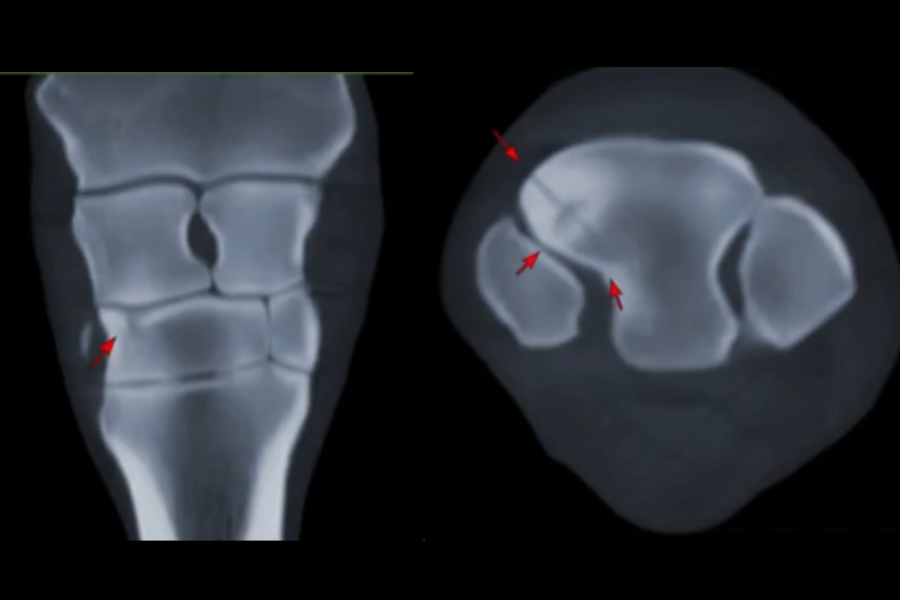

• Standing CT is the best way to get diagnostic quality images of an injury to your horses head, neck or lower limbs. The procedure is much faster and produces higher quality images than traditional x-rays and does not require general anesthesia, which is required for conventional CT.

• For most cases, x-rays are not needed if you elect to have a CT scan. CT imaging is far quicker and provides a complete and comprehensive assessment, most often finding far more detail than you can expect to see from conventional planar x-ray images.

• Lameness and musculoskeletal issues are common in horses and can be hard to diagnose. Because of the high quality of Equina images, it is particularly helpful in finding the specific causes of lameness and other lower limb problems.

• Standing CT is better than other imaging modalities because of the combination of the ease of image acquisition and the quality of the images. In about 30 minutes, your vet can have a comprehensive assessment of the lower limbs, or head and neck of your horse without the risk of general anesthesia. With this detailed information, veterinarians can develop more personalized and effective treatment plans for your horse, leading to quicker recovery and a higher chance of returning to training and performing.